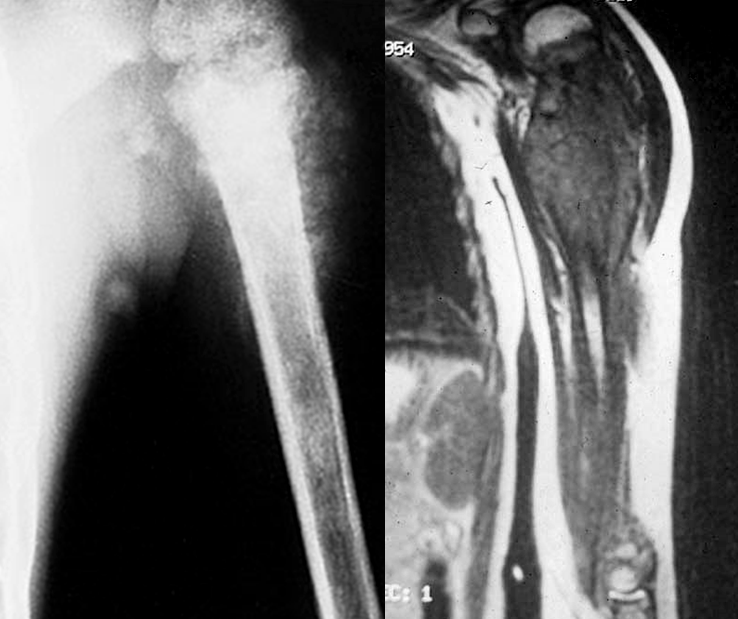

Çocuklarda Kemik ve Eklem İltihapları Günümüzde gerek çocukluk çağındaki aşılama programlarının etkinliğinin çok artmış olması, gerek toplumun beslenme ve sağlık koşullarının giderek iyileşmesi ve son olarak tıbbi olanakların gelişmesi ve yeni antibiyotiklerin devreye girmesi ile kemik-eklem iltihapları eskiye oranla çok daha az görülmekte ve daha kolay tedavi edil...